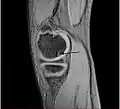

Sagittal MRI: Linear low T1 signal at the articular surfaces of the lateral aspects of the medial condyle of the femur confirms the presence of OCD.

Magnetic resonance imaging (MRI) is useful for staging OCD lesions, evaluating the integrity of the joint surface, and distinguishing normal variants of bone formation from OCD by showing bone and cartilage edema in the area of the irregularity. MRI provides information regarding features of the articular cartilage and bone under the cartilage, including edema, fractures, fluid interfaces, articular surface integrity, and fragment displacement.[37][38] A low T1 and high T2 signal at the fragment interface is seen in active lesions. This indicates an unstable lesion or recent microfractures.[30] While MRI and arthroscopy have a close correlation, X-ray films tend to be less inductive of similar MRI results.[38]